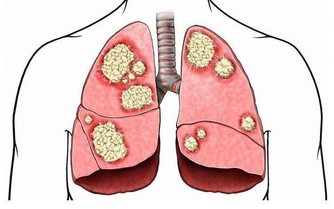

記得剛做住院醫生的時候,那時對卵巢癌患者做化療,

藥物中順鉑已是必備藥,而且現在這個藥還是卵巢癌化療的首選藥。

順鉑這個藥物對改善卵巢癌患者的預後起了很大的作用,

使80年代前的1年成活率不到20%,在使用這個藥後其2年成活率超過80%。

現在這個藥也用於其它惡性腫瘤的化療。

但這個藥有個很大的毒副作用,就是損傷腎臟,像氨基糖甙類抗生素一樣,引起腎小管壞死。

最近10多年,發現卵巢癌患者的化療,只需要化療6個療程就夠了,療效與化療12個療程差不多。

但最近卻一連發現有3位患者,在進行到第4個療程的時候,出現了不同程度的腎功能受損。

當然,我們首先想到的是順鉑對腎臟的損傷,但這幾個病人的腎臟代償能力怎麼就這麼差呢?

帶著這個問題,我在隨訪中對這幾個病人的飲食習慣問了一下,發現她們的確都和我一樣,喜歡吃蘑菇。